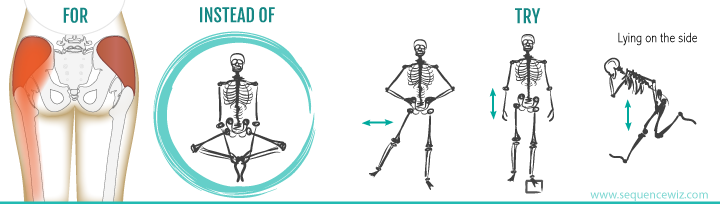

·原因: 疼痛大约在屁股摺痕处。尤其是在你膝盖伸直且将身体向前弯腰时,症状会更明显。这种型态的疼痛表示是连接到骨盆的腘绳肌肌腱受伤,这通常是因为过度的拉扯腘绳肌。(如在瑜伽中:当瑜伽练习者需要保持双腿笔直向前弯曲,然后强迫自己摆姿势时,可能最终会损伤肌腱。)当我们的肌腱受伤,腘绳肌会自然的收缩,试图去保护受伤的肌腱。然而我们认为的是:"腘绳肌紧绷又疼痛,要去伸展它,疼痛自然会消失了",而这样的方式却无法让肌腱修复,反而是重复使其受伤——过度伸展然后再受伤,这样的循环会使复原时间变更长。较好的方式是借由适当地收缩腘绳肌来增加受伤区域的循环,如果可以的话,做简单轻微的伸展。当疼痛急性期结束后,你可以慢慢增加伸展的角度。您的朋友或患者中,是否有人向你这样抱怨过:我的髋部在走路、睡觉时会痛,物理治疗师建议他作核心运动,骨科医师诊断他是梨状肌症候群,也试过请按摩师放松他紧绷的髂胫束。经过仔细的检查后,确认了他疼痛的位置,疼痛的症状都指向无力的外展肌群,造成骨盆位置不良,导致某些肌肉群去代偿。当开始训练他的外展肌群,很快地他的疼痛就不见了。此型态的疼痛通常会出现在臀部外侧或上侧,可能会向下至大腿的外侧。它通常是在散步跟晚上侧躺在患侧时更糟。薄弱的外展肌群,紧绷的髂胫束可能是引起疼痛的一种因素。这种疼痛常被认为是髂胫束的问题,所以借由伸展髂胫束,或用滚筒去放松,这会非常有效,但并没有解决问题的根源-外展肌无力,除非你去加强肌力,否则问题会一再出现。你需要锻炼你的髋外展肌,可以利用单脚站,另一侧大腿对抗重力做髋外展动作,两侧轮流施行,让髋外展肌做为稳定以及动作的功能角色。大家知道坐骨神经分布的范围到底有多大吗?它是你的身体里最长的一条神经,从下段脊椎一路延伸到脚,而且它也非常的粗,大概就像是你的小指头一样粗,穿过你的脊椎与髋关节。因为这条神经粗又长,它可能在很多地方被挤压到,而造成类似坐骨神经痛的症状。两个常见被挤压位置在下背部(腰椎椎体间)跟紧绷的梨状肌下面。梨状肌是一条很小的肌肉,当它太紧绷时可能会造成很多困扰。它位于髋部深处,在髋关节弯曲状态下,负责带动髋关节外转跟外展。紧绷的梨状肌会造成屁股痛,但当它压迫到通过梨状肌下面的坐骨神经时,就会使情况变得更糟。疼痛通常会出现在臀部中间的位置、下背部,或任何坐骨神经通过的地方。症状也有可能是脚麻或无力。如果是因为椎间盘突出引起的坐骨神经痛,是比较大的问题,超过我们本篇所要介绍的范围,在物理治疗师的指导下,加强核心肌群的运动是个不错的方式。如果疼痛是因为紧绷的梨状肌,我们可以着手于放松紧绷的肌肉。·较好的方式:利用我们常见的”收缩-放松-伸展原则”(Contract-Relax-Stretch principle)步骤①:从收缩周围肌肉开始(尤其是臀大肌),来增加此区域的血液循环。步骤②:然后我们可以轻轻的收缩梨状肌 (contract the piriformis ),让它慢慢放松掉原本慢性的收缩(如果不会感到疼痛),搭配温和的伸展。我们可以借鉴瑜伽中的动作,像是勇者式二(Virabhadrasana 2)、侧三角伸展式(Utthita Parsvakonasana)跟蚌蛤式都可以让梨状肌收缩,而在站姿下利用椅子做扭转动作,以及半鱼王式(Ardha Matsyendrasana)是伸展梨状肌最好的选择,因为此姿势会让你的脚处于弯曲、内收,但不会外转的姿势,这对于梨状肌是比较温和的姿势。步骤③:当你觉得你已经准备好在伸展加入外转的动作时,你可以选择穿针引线式(Thread-the-needle pose)来取代鸽式(Pigeon)或牛面式(Gomukasana),这会让使梨状肌受到较小的力矩。当你练习这些动作后,你就可以试着做鸽式(Pigeon)或牛面式(Gomukasana)。PS:但有些学生即使练习很久也还是没办法完成鸽式或牛面式。此外,由于过紧的内收肌群会使髋关节呈现内转姿势,使梨状肌产生额外的压力进而压迫到神经,所以也可使用相同的方式来舒缓内收肌群的慢性紧缩。紧绷的腘绳肌也会造成坐骨神经受压迫,所以对于缓解此肌群的张力也是很有效果的。请记住,即使最简易的腘绳肌伸展运动也可能造成一位有坐骨神经痛症状的人极大地疼痛,所以建议用前面提及到第一种臀部疼痛的腘绳肌伸展原则。 请记住,一个疼痛症状,有可能是许多原因造成的。如果您的疼痛在你经过一番努力后,仍然存在,应该是要去寻求专业建议的时候了。